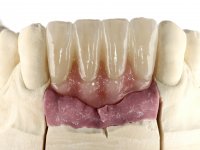

After an imaging study, the placement of two implants of 3.3 mm in diameter and 10 mm in length was planned. On the day of surgery, teeth 42 and 32 were extracted and the implant was removed. The implants were placed in the area of the alveoli, taking care to slightly lingualize their positioning. An impression was made using the open tray technique with the flap open for the fabrication of the immediate provisional bridge. While the impression was taken to the laboratory, tall healing screws were placed and the surgical wound was sutured. The patient waited 2 hours in the waiting room while the temporary bridge was made in the laboratory. An immediate screw-retained provisional bridge was placed and its seating was controlled by imaging. After 3 months, the final impression was made using an open tray technique. In this consultation, we took the opportunity to polish the temporary bridge with rubber cups so that the soft tissues could mature in better conditions. Information was collected to better characterize the monolithic structure in Zr. Color guides were used for the coronal and gingival ceramics. In the laboratory, a bridge was made in Zr. bolt-on that has been carefully characterized. After approval by the patient, it was definitively placed in the mouth. Tightening was performed with a dynamic wrench with a torque of 35 N. The holes were covered with Teflon and filled with composite resin.